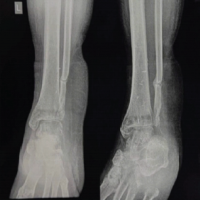

Radiographs revealed diffuse soft-tissue shadow around the ankle with posterior osteophytes in the ankle joint (Fig. 1 and 2).